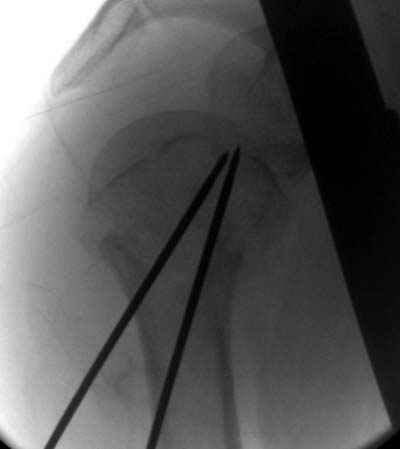

Женя, а как ты водишь спицы, в смысле, как делаешь входное отверстие, и как в него проводишь V-спицу? А то о дна из спиц, та, у которой не дошла до головки одна палочка буквы V, как-то выглядит на рентгенограмме, как будто или через очень большое отверстие введена, или каждая половинка через отдельные отверстия.

Мне кажется, проблема в том, что не все концы спиц зашли в головку, и зашедшие - недостаточно далеко прошли.

Спицы провожу по передней и задней поверхностям плечевой кости через 4,5 мм отверстия на разных уровнях.

Уточни - обе части буквы V вводишь в одно отверстие? А то по снимкам выглядит, что в разные.

V-спица проводится через 4,5 мм отверстие. Видимо, из-за разной длины вторая половина спицы *пролетела* мимо отверстия, что и привело к вторичному смещению костных фрагментов.